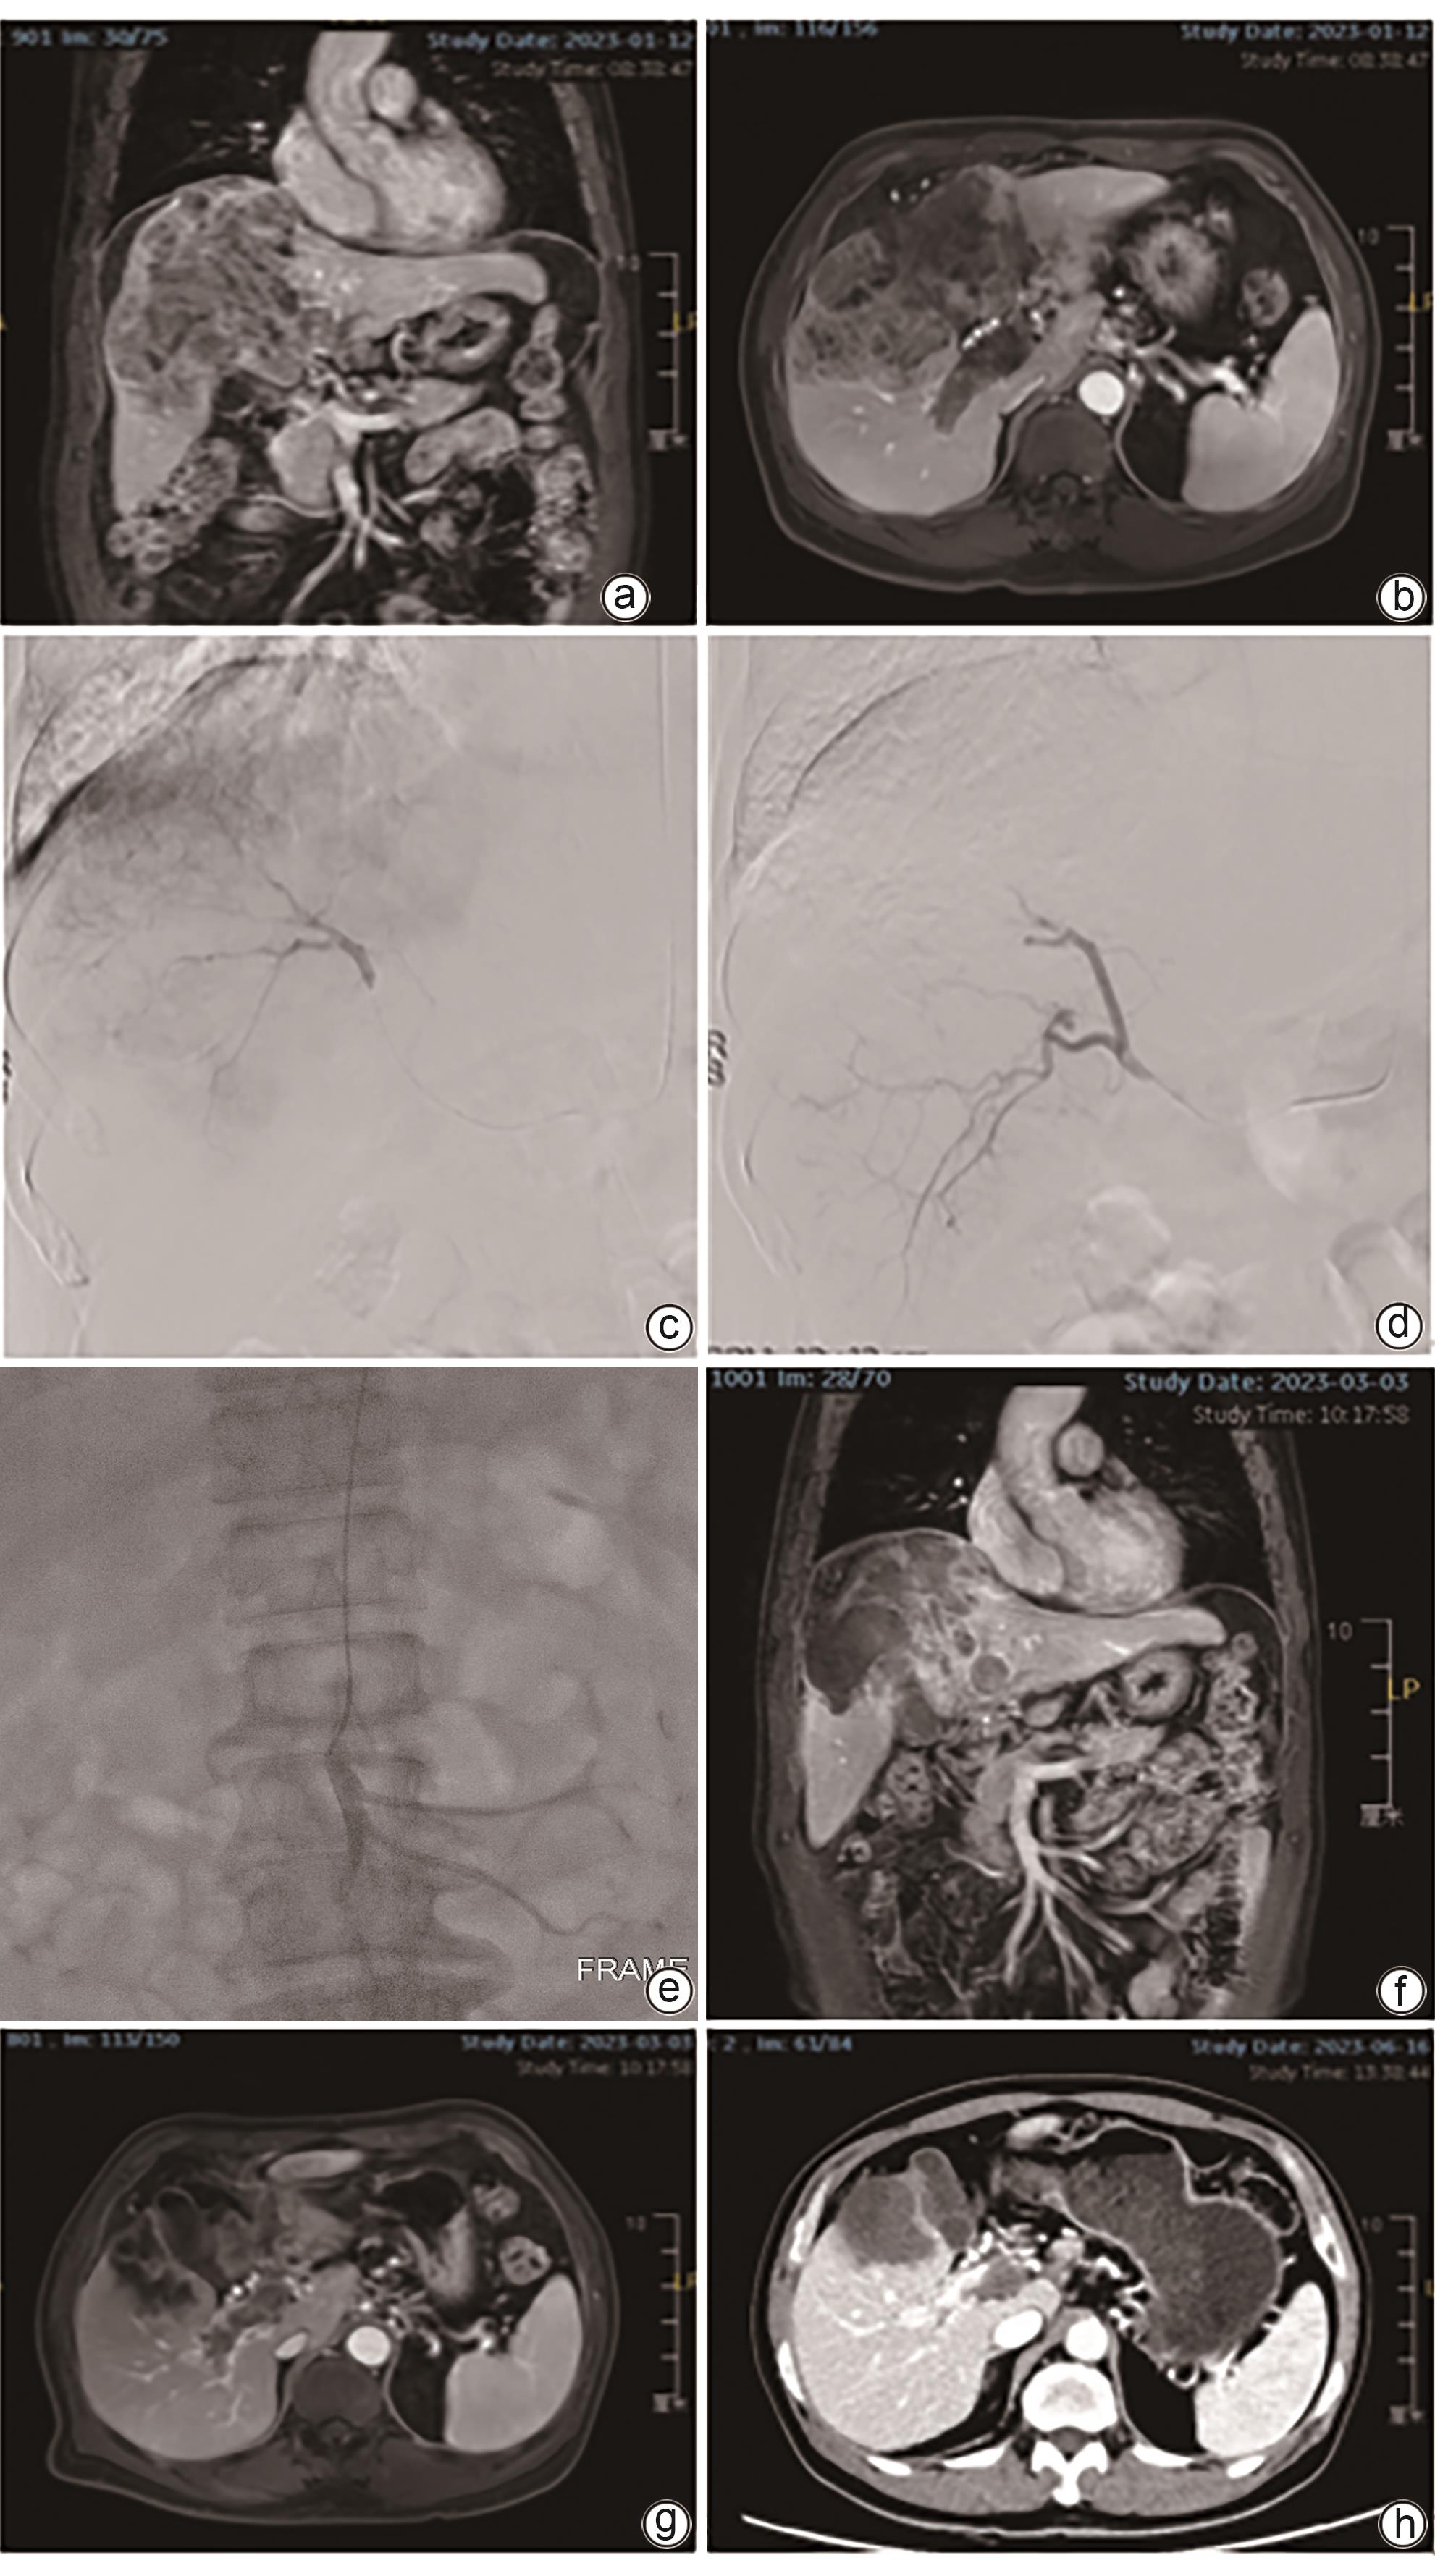

载药微球经导管动脉化疗栓塞术联合肠系膜上动脉灌注化疗治疗肝细胞癌合并门静脉癌栓的效果分析

黄乾鑫, 神斌, 肖晋昌, 高志康, 吕墩涛, 李艳, 徐浩, 张庆桥

2024, 40(12): 2457-2463. DOI: 10.12449/JCH241216

摘要(1412) HTML (289) PDF (1735KB)(62)

摘要:

目的  对比分析载药微球经导管动脉化疗栓塞术(D-TACE)联合肠系膜上动脉灌注化疗与单纯D-TACE治疗肝细胞癌合并门静脉癌栓(PVTT)的效果。  方法  回顾性分析徐州医科大学附属医院2022年1月—2023年12月行介入治疗的肝细胞癌合并PVTT的患者资料,其中采用D-TACE联合肠系膜上动脉灌注化疗的患者15例(观察组)。按1∶1进行倾向性匹配后入选单纯D-TACE治疗的患者15例(对照组)。术后1、2、3个月及以后每3个月行上腹部增强MRI评估肝脏肿瘤及PVTT情况。对比分析两组患者客观缓解率(ORR)、疾病控制率(DCR)。计量资料两组间比较采用成组t检验或Mann-Whitney U检验,术前、术后资料比较采用配对t检验或Wilcoxon检验。计数资料两组间比较采用χ2检验。采用Kaplan-Meier曲线计算累积生存率,并使用Log-rank检验比较两组差异。  结果  两组患者治疗技术成功率100%,术后均无严重并发症。全部患者随访3~26个月,平均(10.5±6.7)个月。术后3个月,观察组和对照组肝脏肿瘤的ORR(73.3% vs 53.3%)和DCR(93.3% vs 80.0%)差异均无统计学意义(P值均>0.05);观察组PVTT的ORR(46.7% vs 13.3%)和DCR(100% vs 73.3%)均显著高于对照组(χ2值分别为3.968、4.615,P值分别为0.046、0.032)。观察组和对照组患者累积3、6、12个月无进展生存率分别为93.3%、86.2%、68.9%和80.0%、62.2%、24.9%(P=0.028);累积3、6、12个月总生存率分别为100%、88.9%、88.9%和93.3%、85.6%、70.0%(P=0.340)。  结论  与单纯D-TACE相比,D-TACE联合肠系膜上动脉灌注化疗在治疗肝细胞癌合并PVTT方面显示了更好的近期疗效。